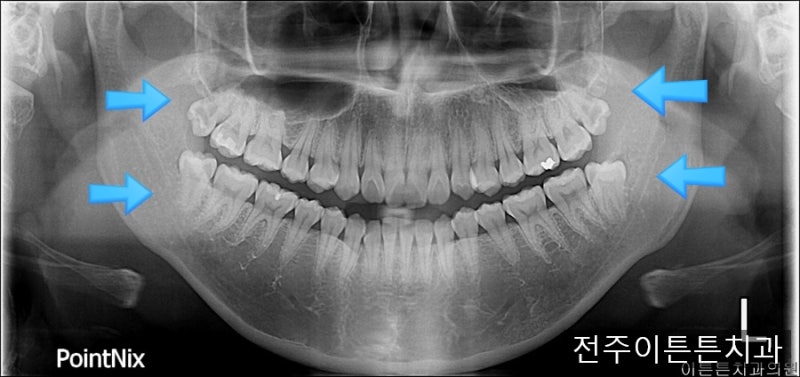

양쪽 아래 사랑니를 보면 맹출 방향이 역방향임을 알 수 있다. 사랑니를 앓는 환자들이 나중에 치과에 와서 사진을 보고 설명을 하면 치아가 수평이 아닌 것을 다행이라고 생각하는 경우가 많다. 그러나 치아가 뒤를 향하고 있을 때는 뒤쪽의 턱뼈가 치아를 매우 강하게 지지하고, 앞쪽과 반대 방향, 즉 발치 방향이 되어 있어 장치 접근이 어렵다. 위의 경우 치아의 뿌리도 많이 휘어져 있고 치아가 매우 커서 치아를 발치하기 어려운 상황에 해당합니다. 이 부분은 환자에게 치아발치를 했다고 충분히 설명을 드렸는데요, 위의 예에서는 사진상으로 양쪽 아래 사랑니와 오른쪽 위(실제로는 왼쪽 위) 사랑니를 포함하여 2~3개의 사랑니를 발치하였습니다.

사진 왼쪽 하단에 있는 사랑니였는데 뿌리가 휘고 머리가 너무 커서 치아가 여러 조각으로 쪼개져 뽑혔습니다. 치근이 뼈에 단단히 부착되어 발치가 어려웠지만 치근을 포함한 모든 치아가 깨끗하게 발치되었습니다. 사랑니 발치의 난이도는 엑스레이로 대략적으로 예측할 수 있지만 실제로는 치아 뿌리의 유착 정도와 환자 뼈의 경도도 중요하기 때문에 발치에는 실제로 시간이 걸린다. 시기에는 약간의 차이가 있을 것입니다. 골드내추럴치과에서는 다양한 사랑니 발치 경험 사례를 통해 가장 빠르고 불편함이 적은 사랑니 발치를 위해 노력하고 있습니다. 공포감이 강해 사랑니 발치를 미루게 되면 나중에는 염증으로 인해 발치시 더 큰 불편함을 유발할 수 있으며 앞니에도 악영향을 미칠 수 있습니다. 이는 보통 사람들이 걱정하는 것과는 다르고, 평소에 쉽게 할 수 있는 일이니 두려워하지 마시고, 다른 치아에 염증이 생기거나 다른 치아 건강 문제로 진행되기 전에 적절한 상담과 치료를 통해 치아 건강 문제를 보호하시기 바랍니다. .나는 희망